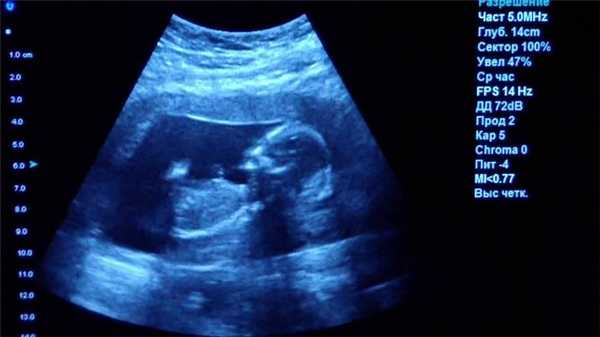

Ультразвуковое исследование (УЗИ)

Главное преимущество такого способа исследования — безопасность. УЗИ можно делать даже беременным женщинам, кроме того, приборы УЗИ-приборы мобильны, их легко можно поставить в палате пациента, чтобы наблюдать за состоянием органов и кровотока в режиме реального времени.

Однако УЗИ не может обеспечить картинку высокой чёткости, поэтому использование этого метода исследование ограничено, например, при помощи УЗИ нельзя диагностировать заболевания ЖКТ.

Что покажет УЗИ

Ультразвуковое исследование или УЗИ - это широко распространенный вид обследования, активно применяемый в диагностических центрах СПб. В ходе данной процедуры диагностика проводится с помощью ультразвуковых волн. Проходя через границы тканей различной плотности, ультразвук по-разному отражается от них. Ультразвуковая установка имеет датчик, который посылает ультразвуковой сигнал, а затем фиксирует ответ и переводит его в графическое изображение. Таким способом врачи могут хорошо обследовать:

- органы малого таза;

- органы брюшной полости;

- лимфоузлы и молочные железы;

- мягкие ткани;

- сосудистую систему.

К сожалению, серьезным препятствием для ультразвука являются кости, через которые сигнал пробиться не может. Поэтому малоинформативным является

Основным достоинством УЗИ является отсутствие каких-либо противопоказаний и ценовая доступность. По диагностической ценности и точности УЗИ безусловно уступает МРТ и КТ, однако является приоритетным профилактическим и скрининговым методом обследования для многих заболеваний, включая патологии мочеполовой системы у мужчин и женщин, рака молочных желез и органов брюшной полости, воспалений мягких тканей.

Важно знать, что ни УЗИ, ни МРТ не сопряжены с лучевой нагрузкой. Поэтому при наличии показаний оба метода разрешены к применению во время беременности, при кормлении грудью и в педиатрической практике. Оба вида диагностики неинвазивны и безболезненны. Однако при проведении МРТ врач удаляется в другое помещение, а с пациентом поддерживает связь через наушники.